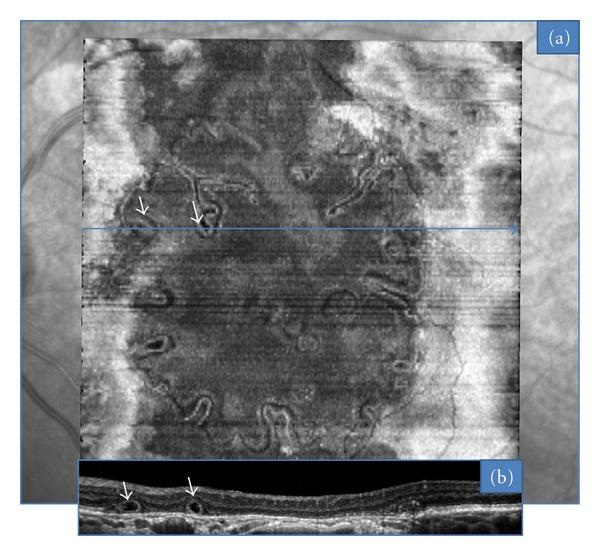

Purpose. "En face" is an emerging imaging technique derived from spectral domain optical coherence tomography (OCT). It produces frontal sections of retinal layers, also called "C-scan OCT." Outer retinal tubulations (ORTs) in age-related macular degeneration (AMD) are a recent finding evidenced by spectral-domain OCT. The aim of this study is to characterize the morphology of ORT according to the form of AMD, using "en-face" spectral domain OCT. Methods. "En face" OCT imaging was prospectively performed in 26 consecutive eyes with AMD that also had ORT. Results. There were 15 neovascular, 8 atrophic, and 3 eyes with a mixed (fibrotic and atrophic) form of AMD. Among the neovascular group, the most frequent tubulation pattern on "en-face" OCT was a branching network emanating from a fibrovascular scar; we term this pattern as "pseudodendritic." It did not require treatment when observed as an isolated finding. In all cases of atrophic AMD, the tubular network was located at the edge of the geographic atrophy area, and formed a "perilesional" pattern. Six atrophic cases showed tubular invaginations inside this area. Conclusion. "En face" OCT is a valuable technique in the diagnosis and followup of macular disease. It revealed the main characteristic patterns of ORT associated with neovascular and atrophic AMD.

目的。“正面成像”是一种源自光谱域光学相干断层扫描(OCT)的新兴成像技术。它能生成视网膜各层的正面图像,也称为“C 扫描 OCT”。年龄相关性黄斑变性(AMD)中的视网膜外层微管(ORTs)是光谱域 OCT 最近发现的现象。本研究的目的是使用“正面成像”光谱域 OCT 根据 AMD 的类型来描述 ORT 的形态。方法。对 26 只连续患有 AMD 且伴有 ORT 的眼睛进行前瞻性“正面成像”OCT 成像。结果。有 15 只新生血管性、8 只萎缩性以及 3 只混合性(纤维化和萎缩性)AMD 眼睛。在新生血管性组中,“正面成像”OCT 上最常见的微管模式是从纤维血管瘢痕发出的分支网络;我们将这种模式称为“假树枝状”。当作为孤立发现观察时不需要治疗。在所有萎缩性 AMD 病例中,管状网络位于地图样萎缩区域的边缘,并形成“病灶周围”模式。6 例萎缩性病例在该区域内显示有管状内陷。结论。“正面成像”OCT 是黄斑疾病诊断和随访中的一项有价值的技术。它揭示了与新生血管性和萎缩性 AMD 相关的 ORT 的主要特征模式。